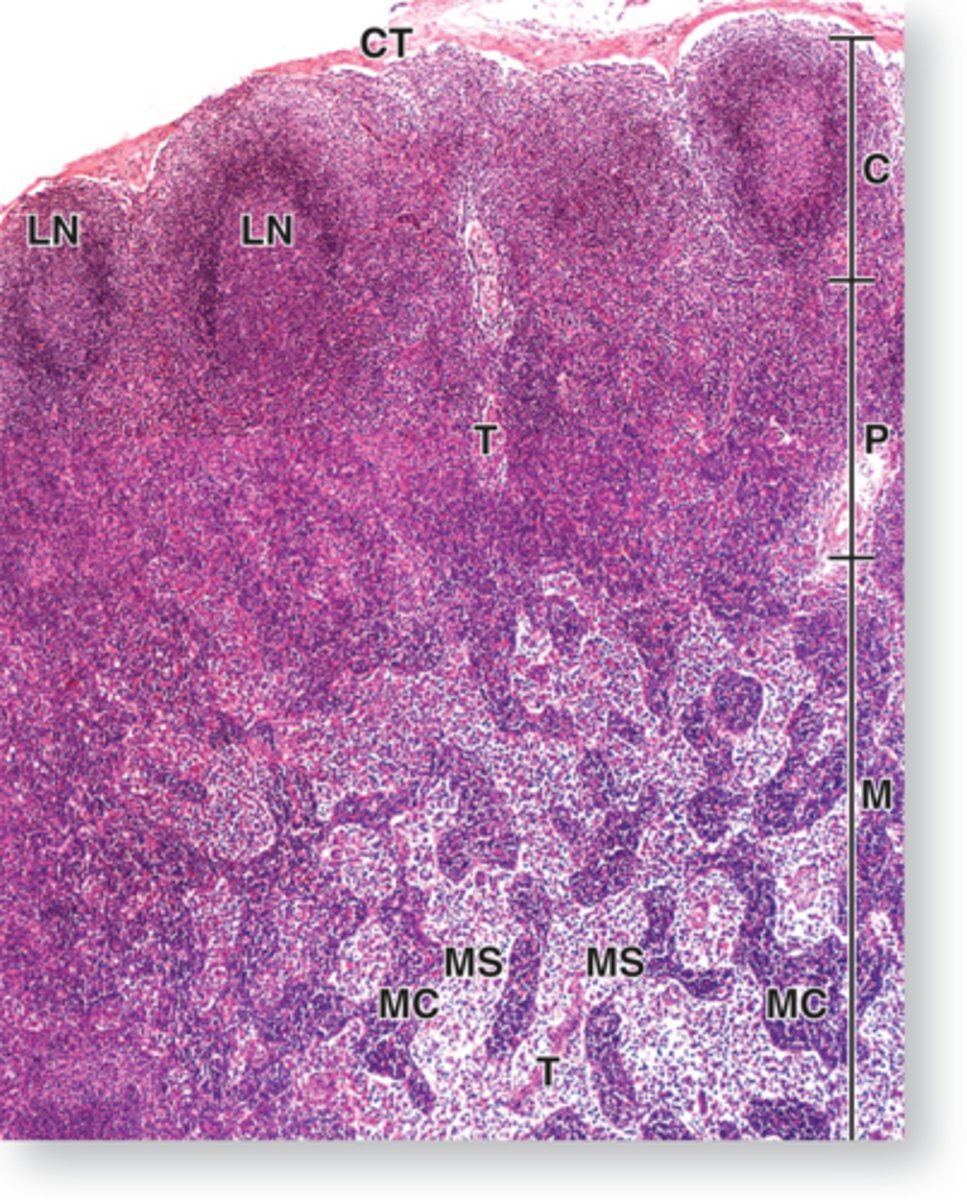

Peyer's patches in ileum

collection of secondary lymphatic nodules

ID structure

secondary lymphatic nodule

black arrow

Peyer's patches